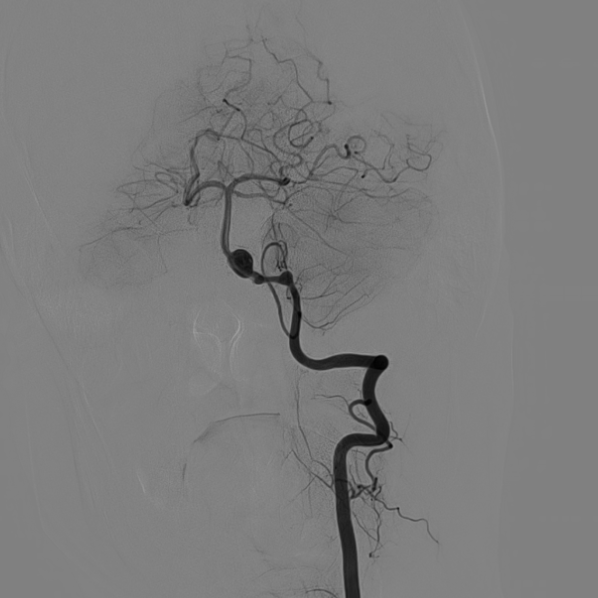

DSA:

3D重建显示基底动脉下部、双椎结合部、左椎多发夹层动脉瘤:

股动脉入路,置入8F长鞘,6F 115cm Navien™ 颅内支撑导管超选至左侧椎动脉V4段。

将Phenom™ 27微导管超选进入左侧大脑后动脉内,释放一枚3.25×35mm Pipeline™ Flex血流导向密网支架,远端定位在动脉瘤以远7mm,在动脉瘤处推密,近端定位在PICA起始部上端或远端,支架打开顺利。导引导管内推注替罗非班12mL,支架导管及微导管常规按摩,促进支架贴壁。